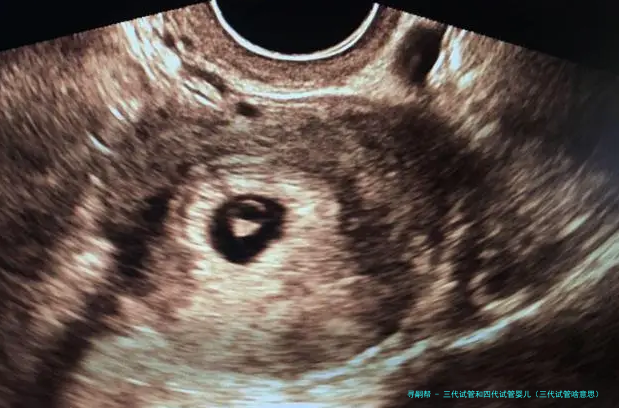

试管婴儿的医学术语称:胚胎转移技术-胚胎移植,其过程是女的一方先使用药物促排卵,再从卵巢内拿出卵子,男方拿出精子,在实验室将精子、卵子结合培育成胚胎,然后又将胚胎转至子宫腔内,令其着床、妊娠。

因此“试管婴儿”可以简单地懂得成由实践室的试管取代了输卵管的功能而称为“试管婴儿”。

利用试管受孕技术发生的婴儿称为试管婴儿,这一些孩子亦是在妈妈的子宫内生长成的。可以说,“试管婴儿技术”等同于“试管受孕”。

试管婴儿即是采用人工方法让卵细胞体体和精子在试管受孕,并进行初期胚胎生长,然后移植到本人体内人宫内发育而降生的婴儿。

“试管婴儿”的完整名称叫做“试管受孕和胚胎移植术”(试管婴儿(IVF)-ET),是一种今世诊疗技术。原理是将卵子、精子分别拿出体外,在人工受控制条件下完成精卵结合,成活后再受精卵移植到母亲身内,着床发育。

试管婴儿道理 “试管婴儿”其实不是真正在试管里长大的婴儿,而是从卵巢内拿出若干个卵子,在实践室里使之们与男方的精子结合,形成胚胎,然后挪动转移胚胎到子宫内,让它位于妈妈的子宫内着床、妊娠。

试管婴儿的道理实际上其实不繁复。在正常情况下,受孕过程是由精子进入女的一方身体内,到达输卵管,在输卵管的壶腹部与卵子碰见结合成受孕卵,然后在子宫着床、生长。